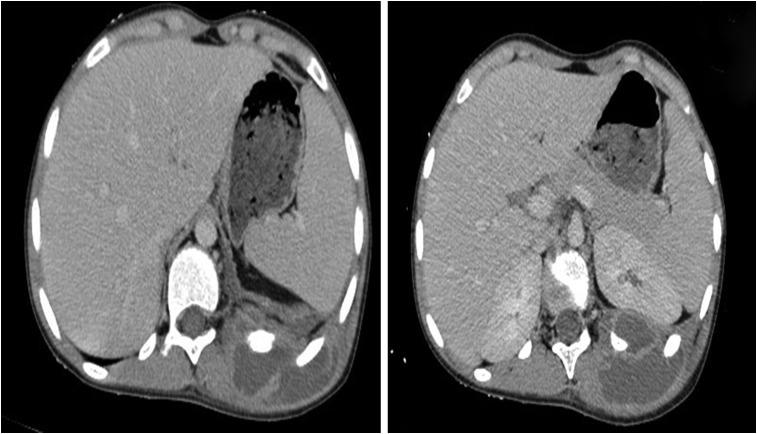

Rib osteomyelitis is a rare disease, occurring in ~1% or less of all cases of haematogenous osteomyelitis. During the last century, 58 cases of rib osteomyelitis were reported in the literature, of which, multiple ribs were involved in only five patients. Because of its rarity and non-specific clinical signs, diagnostic of rib osteomyelitis may be delayed. We report a case of multifocal rib osteomyelitis revealed by a dorsal mass in a healthy 13-year-old female child.

肋骨骨髓炎是一种罕见疾病,在所有血源性骨髓炎病例中发生率约为1%或更低。在上个世纪,文献报道了58例肋骨骨髓炎病例,其中仅有5例累及多根肋骨。由于其罕见性及非特异性临床症状,肋骨骨髓炎的诊断可能会延迟。我们报告一例13岁健康女童因背部肿块而被发现的多灶性肋骨骨髓炎病例。